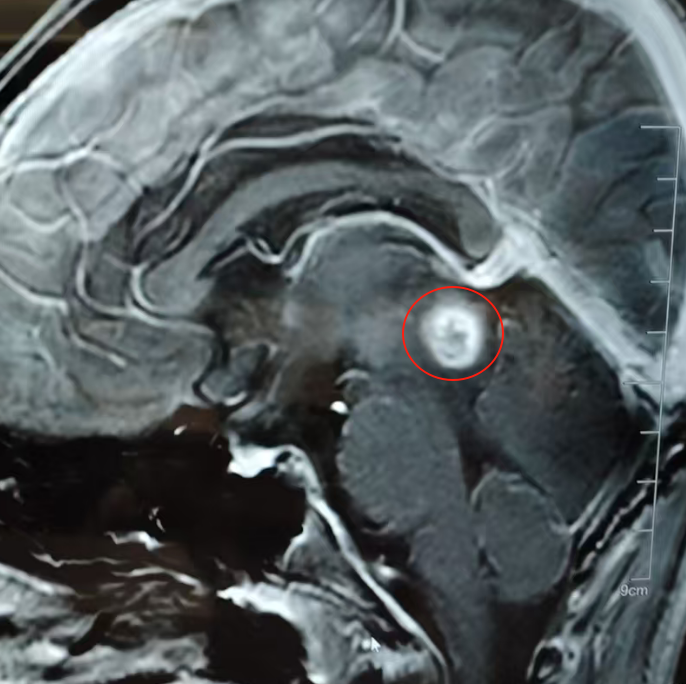

当这位江苏省科技厅省级外国专家工作室首席专家再次走进苏州大学附属儿童医院手术室。在这里,一位12岁的松果体区肿瘤患儿正等待着巴教授的救治。

“你女儿是很严重的脑干出血!”7岁的萌萌已经陷入昏迷,直到术前都没有清醒。连夜被救护车送至苏州大学附属儿童医院,孩子病情有多紧急?“好像随时随地孩子就会(走掉)”。等不起了,父母毅然决然决定寻求巴教授的手术,短短48h后,萌萌顺利手术,萌萌非但不用进ICU,术前的症状也完全消失,她的新生已经开始萌芽:术后2天恢复进食;术后4天进行简单运动;术后7天独立行走;两周后顺利出院;1个月后回归校园、恢复如常。